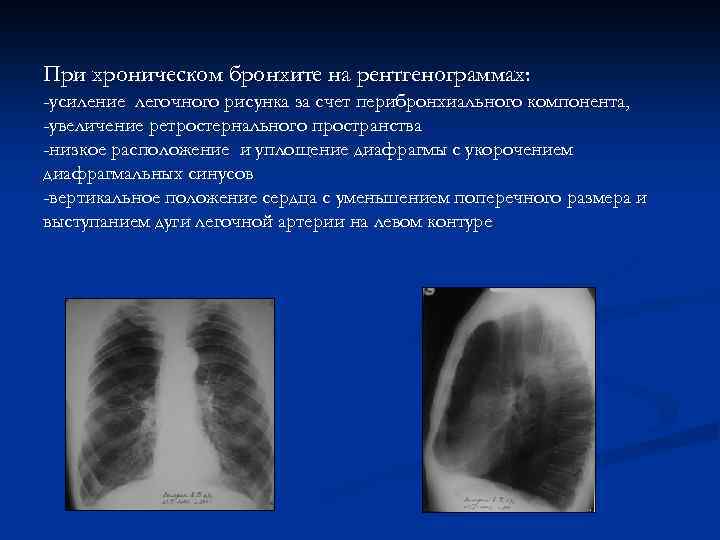

При хроническом бронхите на рентгенограммах: -усиление легочного рисунка за счет перибронхиального компонента, -увеличение ретростернального пространства -низкое расположение и уплощение диафрагмы с укорочением диафрагмальных синусов -вертикальное положение сердца с уменьшением поперечного размера и выступанием дуги легочной артерии на левом контуре